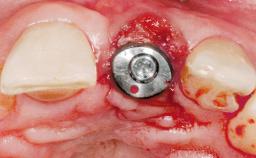

Immediate Flapless Placement of an Implant in a Maxillary Left Central Incisor Site

A 42-year-old female patient was referred to our clinic at the School of Dentistry of the University of São Paulo in November 2004, presenting a deficient restoration in the upper left central incisor. The clinical examination revealed no gingival retraction or any signs of gingival inflammation and, therefore, previous periodontal treatment was not considered. The patient presented a high lip line at full smile and a thin tissue biotype. This combination characterized a high-risk situation from an anatomic point of view, which required careful preoperative planning and cautious surgical execution.

Type of Implants One-Piece

Placement Protocol Immediate implant placement

Tooth Site Maxillary incisor or canine

Socket Morphology Single-root socket

Socket Integrity Sufficient, with intact bone walls